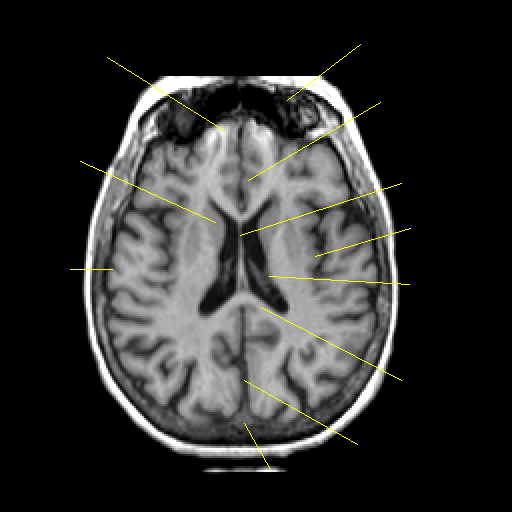

T1-weighted structural MR: Slice 31

Slice 31

Pointers

Labeled